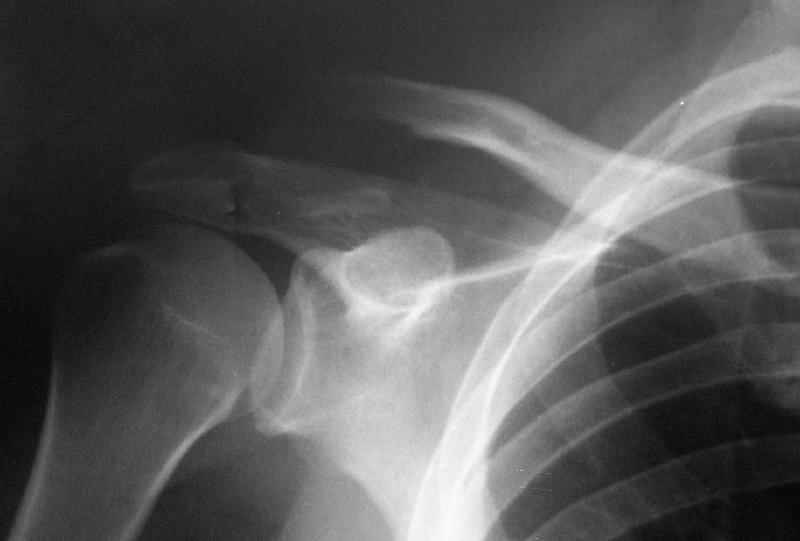

Судя по представленному снимку - существует дистальный фрагмент, который замечательно, вроде бы, связан с акромионом... Что мешает "пришпилить" проксимальный к дистальному и закрепить его при помощи спиц? или как-то по иному (аппарат?)... В любом случае зачем пока идти большим разрезом на ключично-клювовидную связку? почему не пойти от меньшего?

"Толкатель" - укороченная спица с упором. На первичных снимках - оскольчатый перелом, отдельный фрагмент с местом прикрепления кл-кл связки сместился каудально.

Первично правильно сопоставленный перелом (небольшой разрез, спицы) привел бы к тому, что костный фрагмент, отрванный ключично-клювовидной связкой, лег аккурат под своим ложем и тесно к нему... то бишь в итоге сросся бы без проблем... (кстати на вашем снимке костный фрагмент "оскольчатого перелома" консолидирован... то есть даже достигнутая вами несостоятельная фиксация привела к приростанию авульзионно оторванного

фрагмента)

То, что было представлено на вашем снимке - ... - создается впечатление что никакой консолидации в области перелома (основного) достигнуто не было...

Причина? Аппарат? Может быть центральный отломок был смещен кпереди или кзади?

Я бы назвал данный перелом как перелом с костной авульзией ключично-клювовидной связи... Потому как данный фрагмент лежит вне основной зоны перелома...